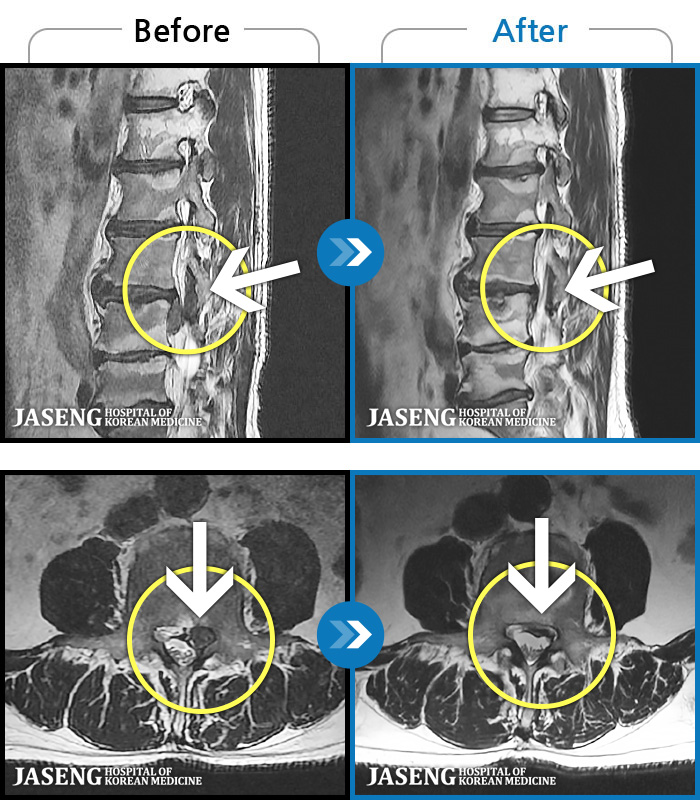

ó 㸮 , ٸ ϰ ־ Ȱ , ߰ ᵵ ڰ Ͽ Ȱ ¼̽ϴ. |